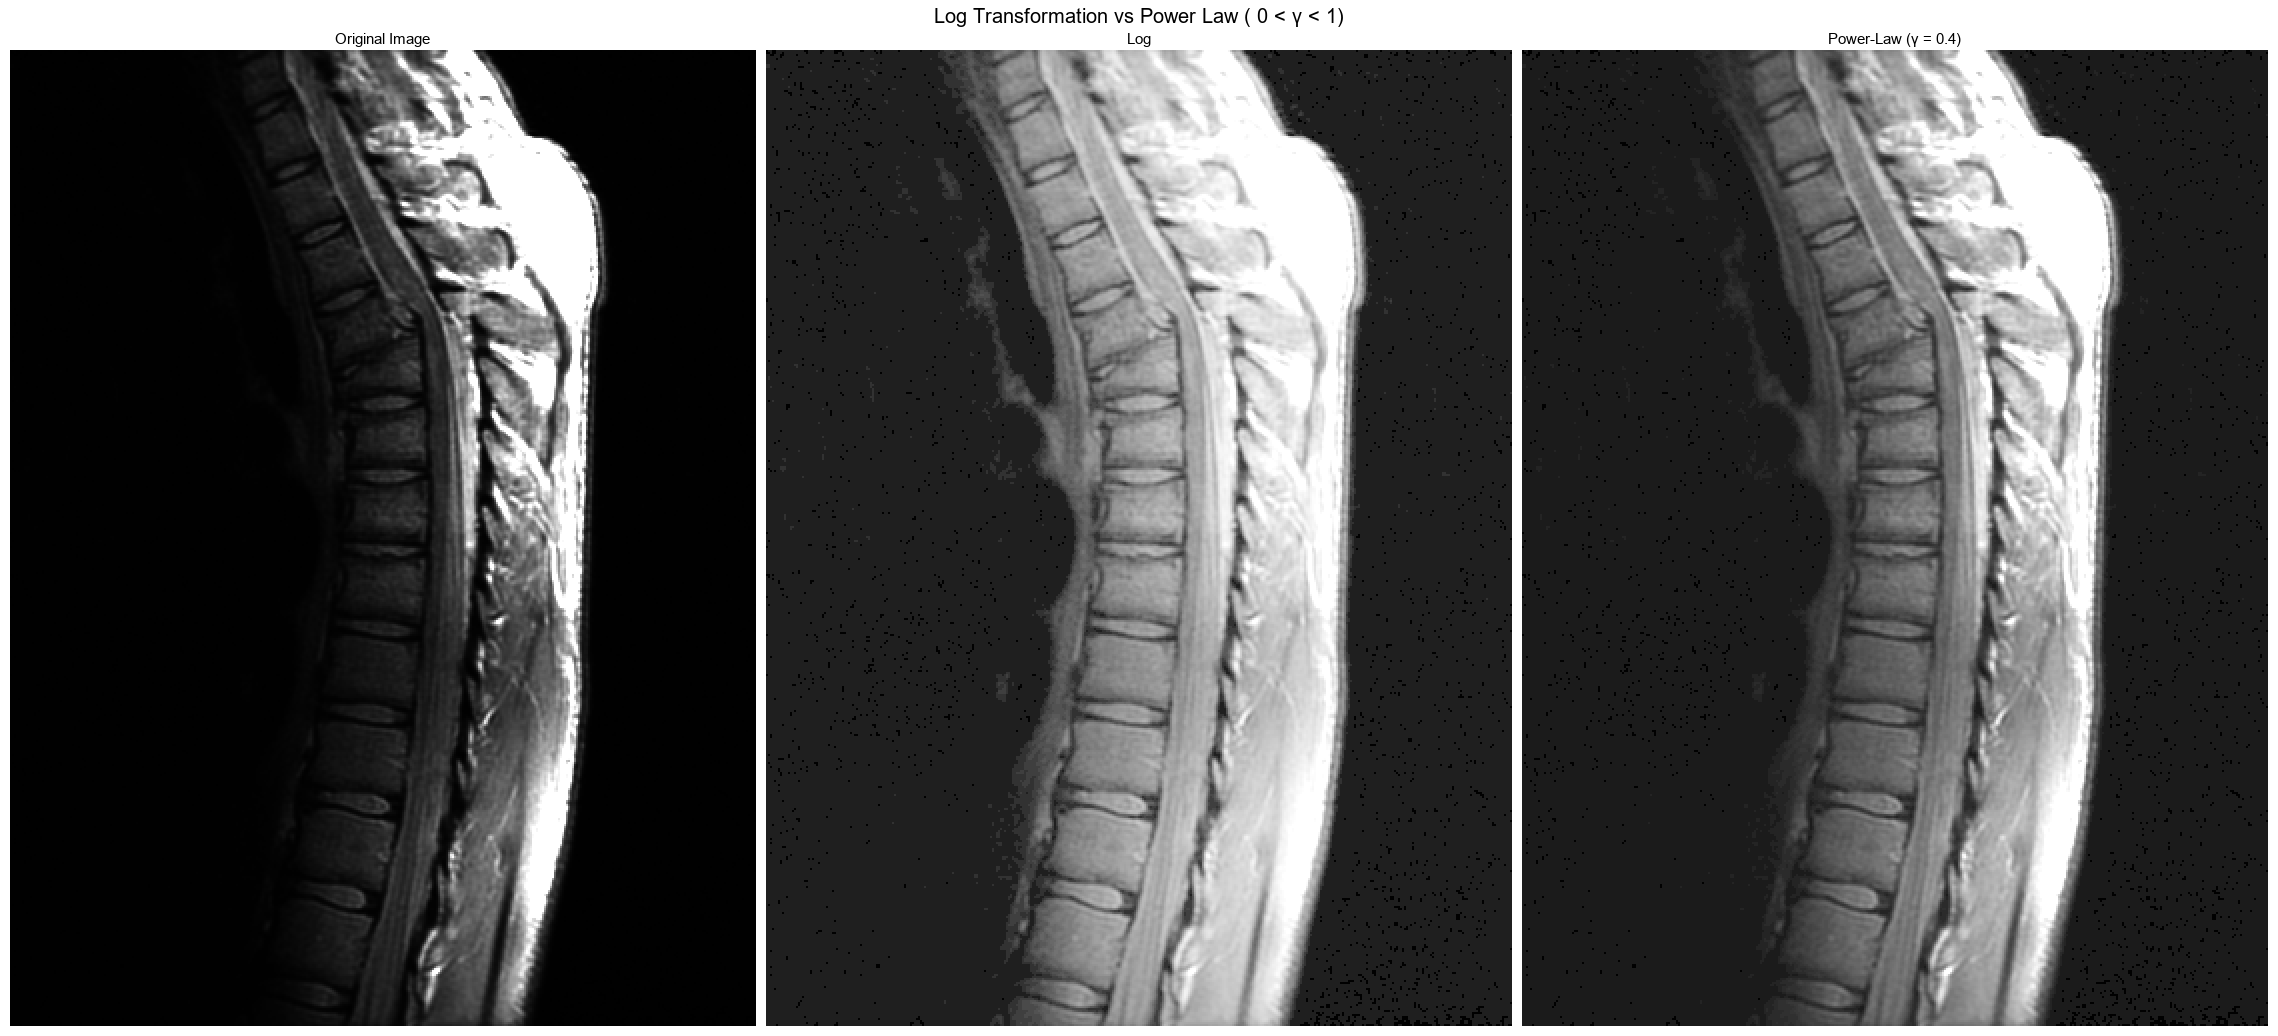

Log 변환은 이미지의 밝기 범위를 균등하게 확장하여 이미지에서 밝기 값이 낮은 영역(어두운 부분)의 세부사항이 크게 강조.

로그 변환된 이미지는 패턴과 질감이 더욱 명확하게 드러남.

PowerLow(γ < 1)는 전체적으로 이미지를 부드럽게 하면서도 중요한 영역의 시각적인 구분을 명확하게 하는데 도움.

Log변환히 확실히 더 Fourier스펙트럼의 디테일을 잘 표현하는거 같음.

로그 변환은 특히 어두운 부분의 디테일을 더욱 선명하게 보이도록 해주는 반면, 밝은 부분은 디테일이 떨어짐.

파워 로 변환은 어두운 부분의 디테일을 살려주면서 밝은 부분도 디테일이 살아있음. 전반적으로 대비를 더욱 증가시켜줍니다.